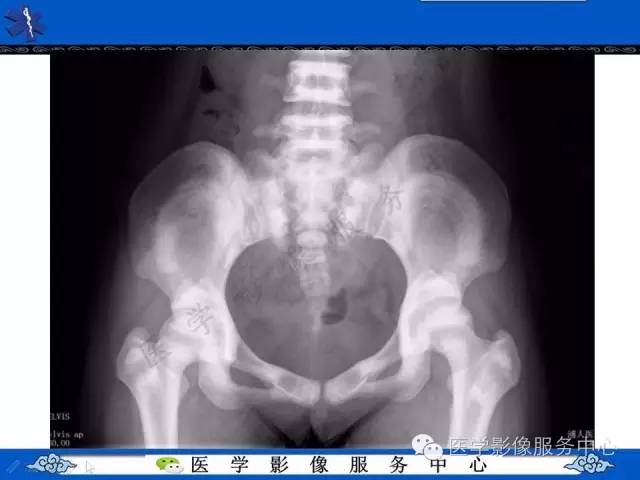

【PPT】石骨症——少见的骨病例,但是过目不忘!